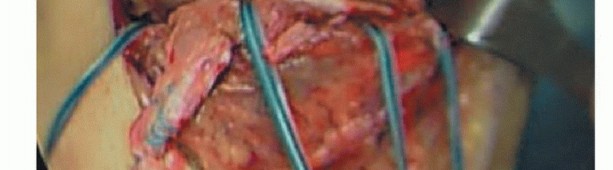

Three or four double-loaded suture anchors are then placed along the medial border of the tibial plateau about 5 mm below the joint line.

The meniscotibial ligament can be secured to the suture anchors, allowing for an excellent repair of the deep MCL along with the coronary ligament and medial meniscus.

The sutures can be left long after the initial knots are tied and also can be used to tie down the superficial MCL (TECH FIG 2).

The superficial MCL is subsequently repaired anatomically to its tibial insertion with suture anchors/spiked screw and washer or staple.

The POL can be imbricated, if patulous, in a pants-over-vest fashion to the repaired MCL.

TECH FIG 2 • Acute suture anchor repair of the deep MCL with imbrication of the capsule. The suture anchors are placed just distal to the joint surface and allow for reefing of the torn deep MCL to the proximal tibia.